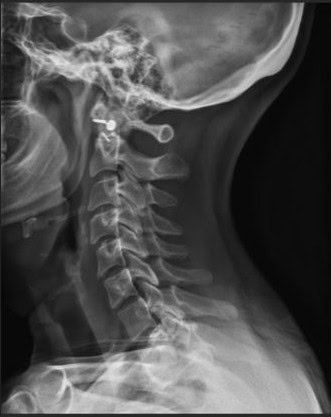

Post Scan